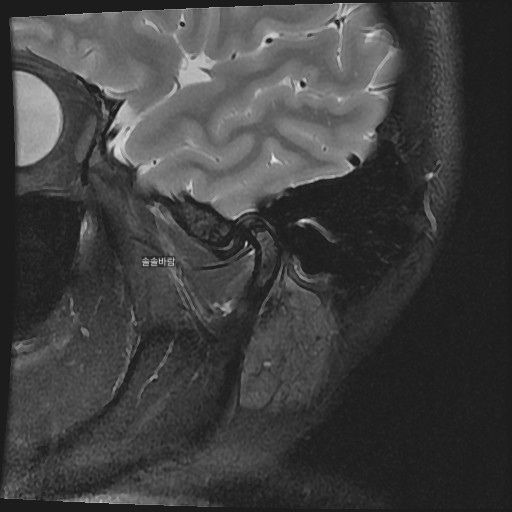

구강내과 턱 MRI 어느 사진이 우측? 좌측?인지 어떻게 보나요? 디스크 두꺼워짐 심한가요?ㅜ

어느 사진이 우측? 좌측?인지 어떻게 보나요?

그리고 사진 상 디스크 두꺼워짐 심한가요?ㅜ

• 1번 째 사진

현재 사진만으로는 정확히 왼쪽이나 오른쪽이다 라고 할 수 없습니다. 이는 데이터 상의 reference가 필요하며 보통은 해당 부위가 질문자님 기준으로 좌측일 가능성이 가장 크나 이는 좌우 반전을 할 수 있기 때문에 무조건 좌측이라고 할 수 없습니다. 현재 개구시와 폐구시에 보았을 때 condyle (아래턱 부위의 일부)가 disc를 넘어가지 못하고 있으며 이러한 경우 개구제한이 있거나 넘어가더라도 소리가 나면서 넘어갈 수 있습니다. 일부 염증도 보이고 있으므로 내과적인 치료를 하셔야 할 것으로 보입니다.